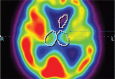

Neuroimaging in the context of examining atypical parkinsonian tauopathies is an evolving matter. Positron emission tomography and single photon emission computed tomography (SPECT) bring tools, which may be reasonable in supplementary examination, however, cannot be interpreted as a criterion standard for correct diagnosis. The aim of this observational study was to assess the differentiating potential of perfusion SPECT in 3 types of atypical parkinsonisms: multiple system atrophy parkinsonian type (MSA-P), corticobasal syndrome (CBS), and progressive supranuclear palsy (PSP). The study was carried out using the comparison of standard deviations of perfusion in patients from these 3 groups. Data obtained from 10 patients with clinical diagnosis MSA-P, 14 patients with CBS and 21 patients with PSP, which were analyzed using Tukey honest significant difference post-hoc test, revealed significant differences of perfusion P < .05 between MSA-P and PSP within the cerebellum and thalamus. No significant differences between CBS and PSP were observed.